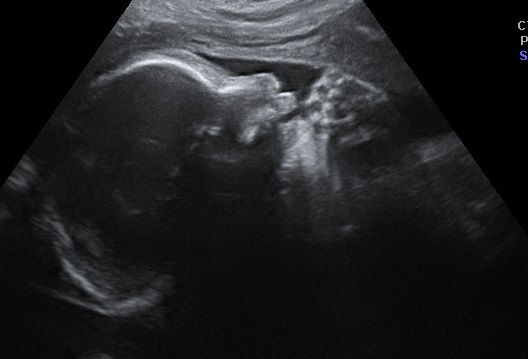

When we found out the gender of our baby, we went to a 3D ultrasound place. We were given a coupon to come back for a discounted rate to have another one done at 30 weeks. We came back and found that the baby was Frank breech and couldn’t really get any good pictures. So they rescheduled one for today. We left Barnes and Nobel and met Sam at the ultrasound place. The good news is that the baby had flipped out of the breech position. The bad news was that she was sleeping and not in a good place for us to see her. They gave Sam juice in hopes that the sugar would wake her up. She drank the juice and we even took a walk around outside. When we came back, we still couldn’t get a good picture of her face. They were, however, able to record her heartbeat for us.

I thought Sam was going to throw up during it. The lady was really trying to get the baby to wake up. She kept rubbing Sam’s belly and poking and massaging her, but the baby would not move. We did get a semi-good profile shot. We also got to see that she has a lot of hair. We got a neat shot of her hand kind of making a fist, but NO good face picture. I admit, I was disappointed. I wanted to be able to take the 3D picture of her face and compare it with her birth picture like so many parents do, but I guess we just need to wait and see her beautiful face when she arrives.